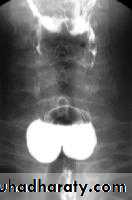

LEFT: Dilated esophagus (arrows) appears as long, well-defined structure paralleling heart RIGHT: Dilated esophagus usually deviates to right. Narrowing (arrow) at hiatus.

LEFT: CT shows dilated esophagus (arrow) that led to esophagram.RIGHT: Esophagram shows narrowing (arrow) at level of hiatus.